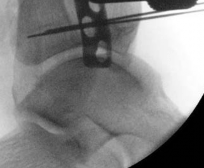

Once reduced, the articular block is secured with independent 3.5 mm or 4.0 mm partially threaded cancellous lag screws. These screws must be placed strategically—typically in the anterior or posterior half of the epiphysis—to leave the central medullary canal completely unobstructed for the nail.

The role of fibular fixation in distal tibia fractures remains a topic of academic debate, but in the context of intramedullary nailing, it is often a highly valuable adjunct. Plating the fibula restores the length of the lateral column and corrects rotational malalignment, effectively converting a highly unstable distal tibia fracture into a more manageable, length-stable pattern.

Image

Fibular fixation is typically performed prior to tibial nailing. An open reduction and internal fixation utilizing a one-third tubular plate or anatomic distal fibula plate is standard. By stabilizing the fibula, the tendency for the distal tibia to drift into valgus during nail insertion is significantly mitigated.